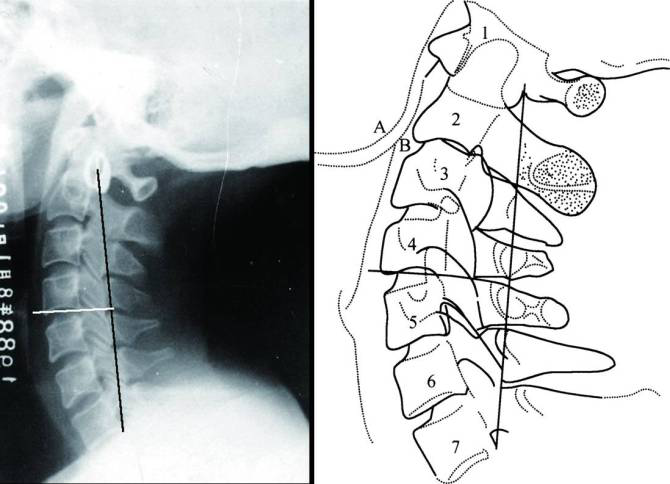

头颅侧位片的描绘与分析(二)微课 2020.07.14